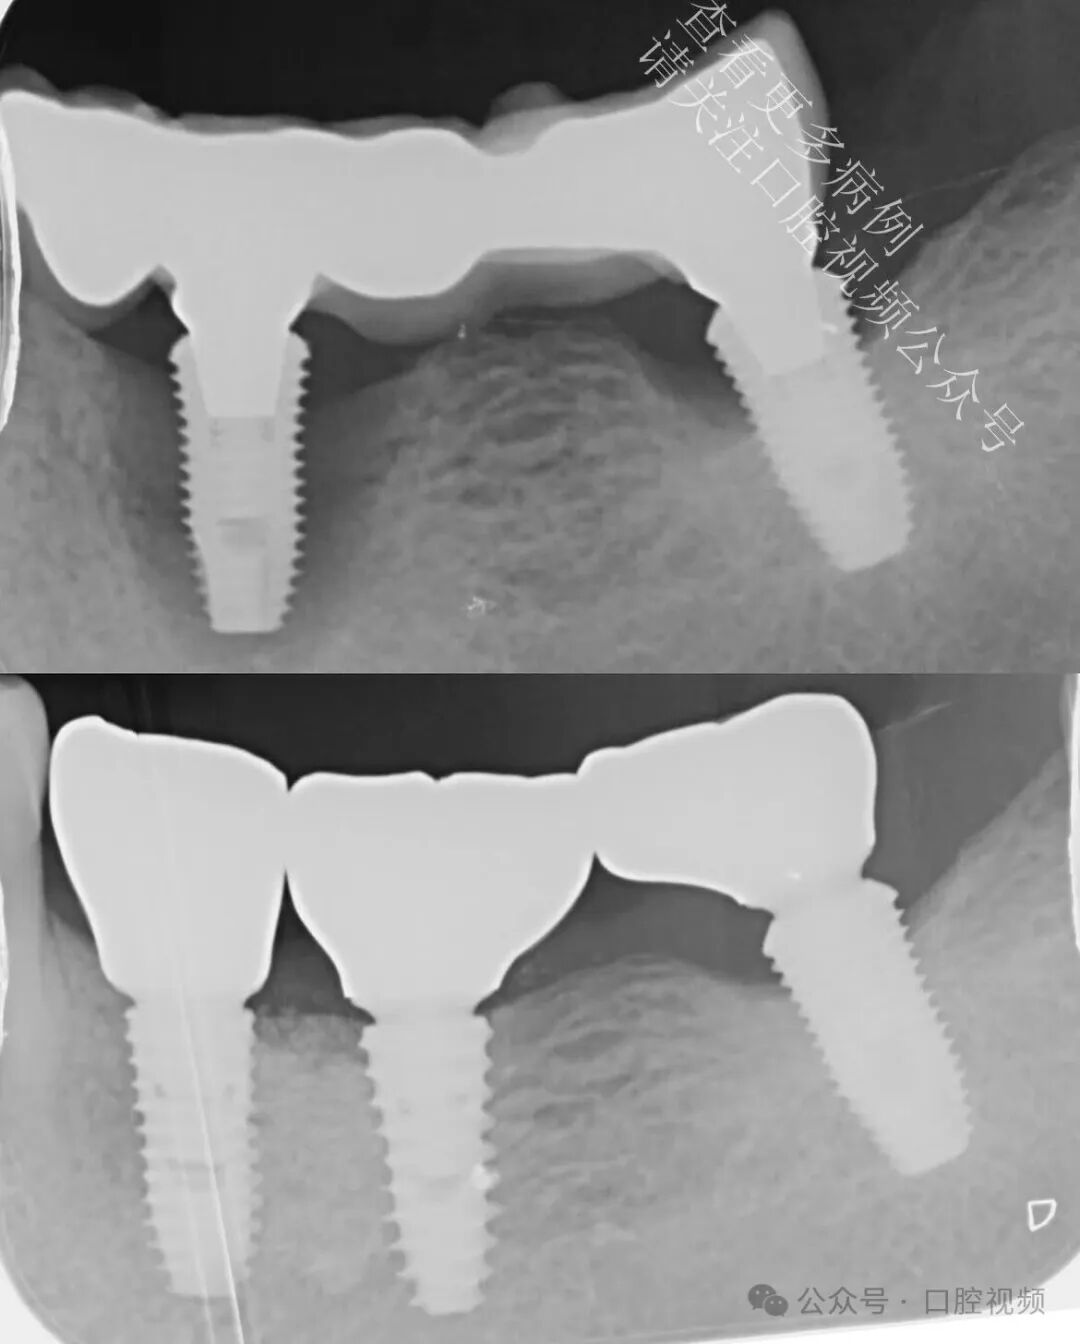

本病例最初计划进行桥体修整,并在近中种植体周围实施垂直+水平向骨增量手术。患者希望保留最后一颗天然牙,因此在等待植骨愈合期间,我将其转诊接受非手术牙周治疗,以稳定软组织。而在愈合过程中,一件令人瞩目的事情发生了:

远中种植体(LL7)开始出现自然的骨增量——此处并未进行任何植骨操作。仅仅是形成了更健康的软组织轮廓、炎症显著减轻,并为生物学自我修复创造了条件。最初,我计划拔除这颗已出现失败迹象的种植体,仅修复 LL5 和 LL6;但鉴于 LL7 周围骨量增加及组织健康状况明显改善,我们最终决定保留并修复该种植体。